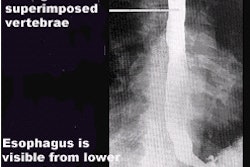

Fluoroscopy procedure volume per site